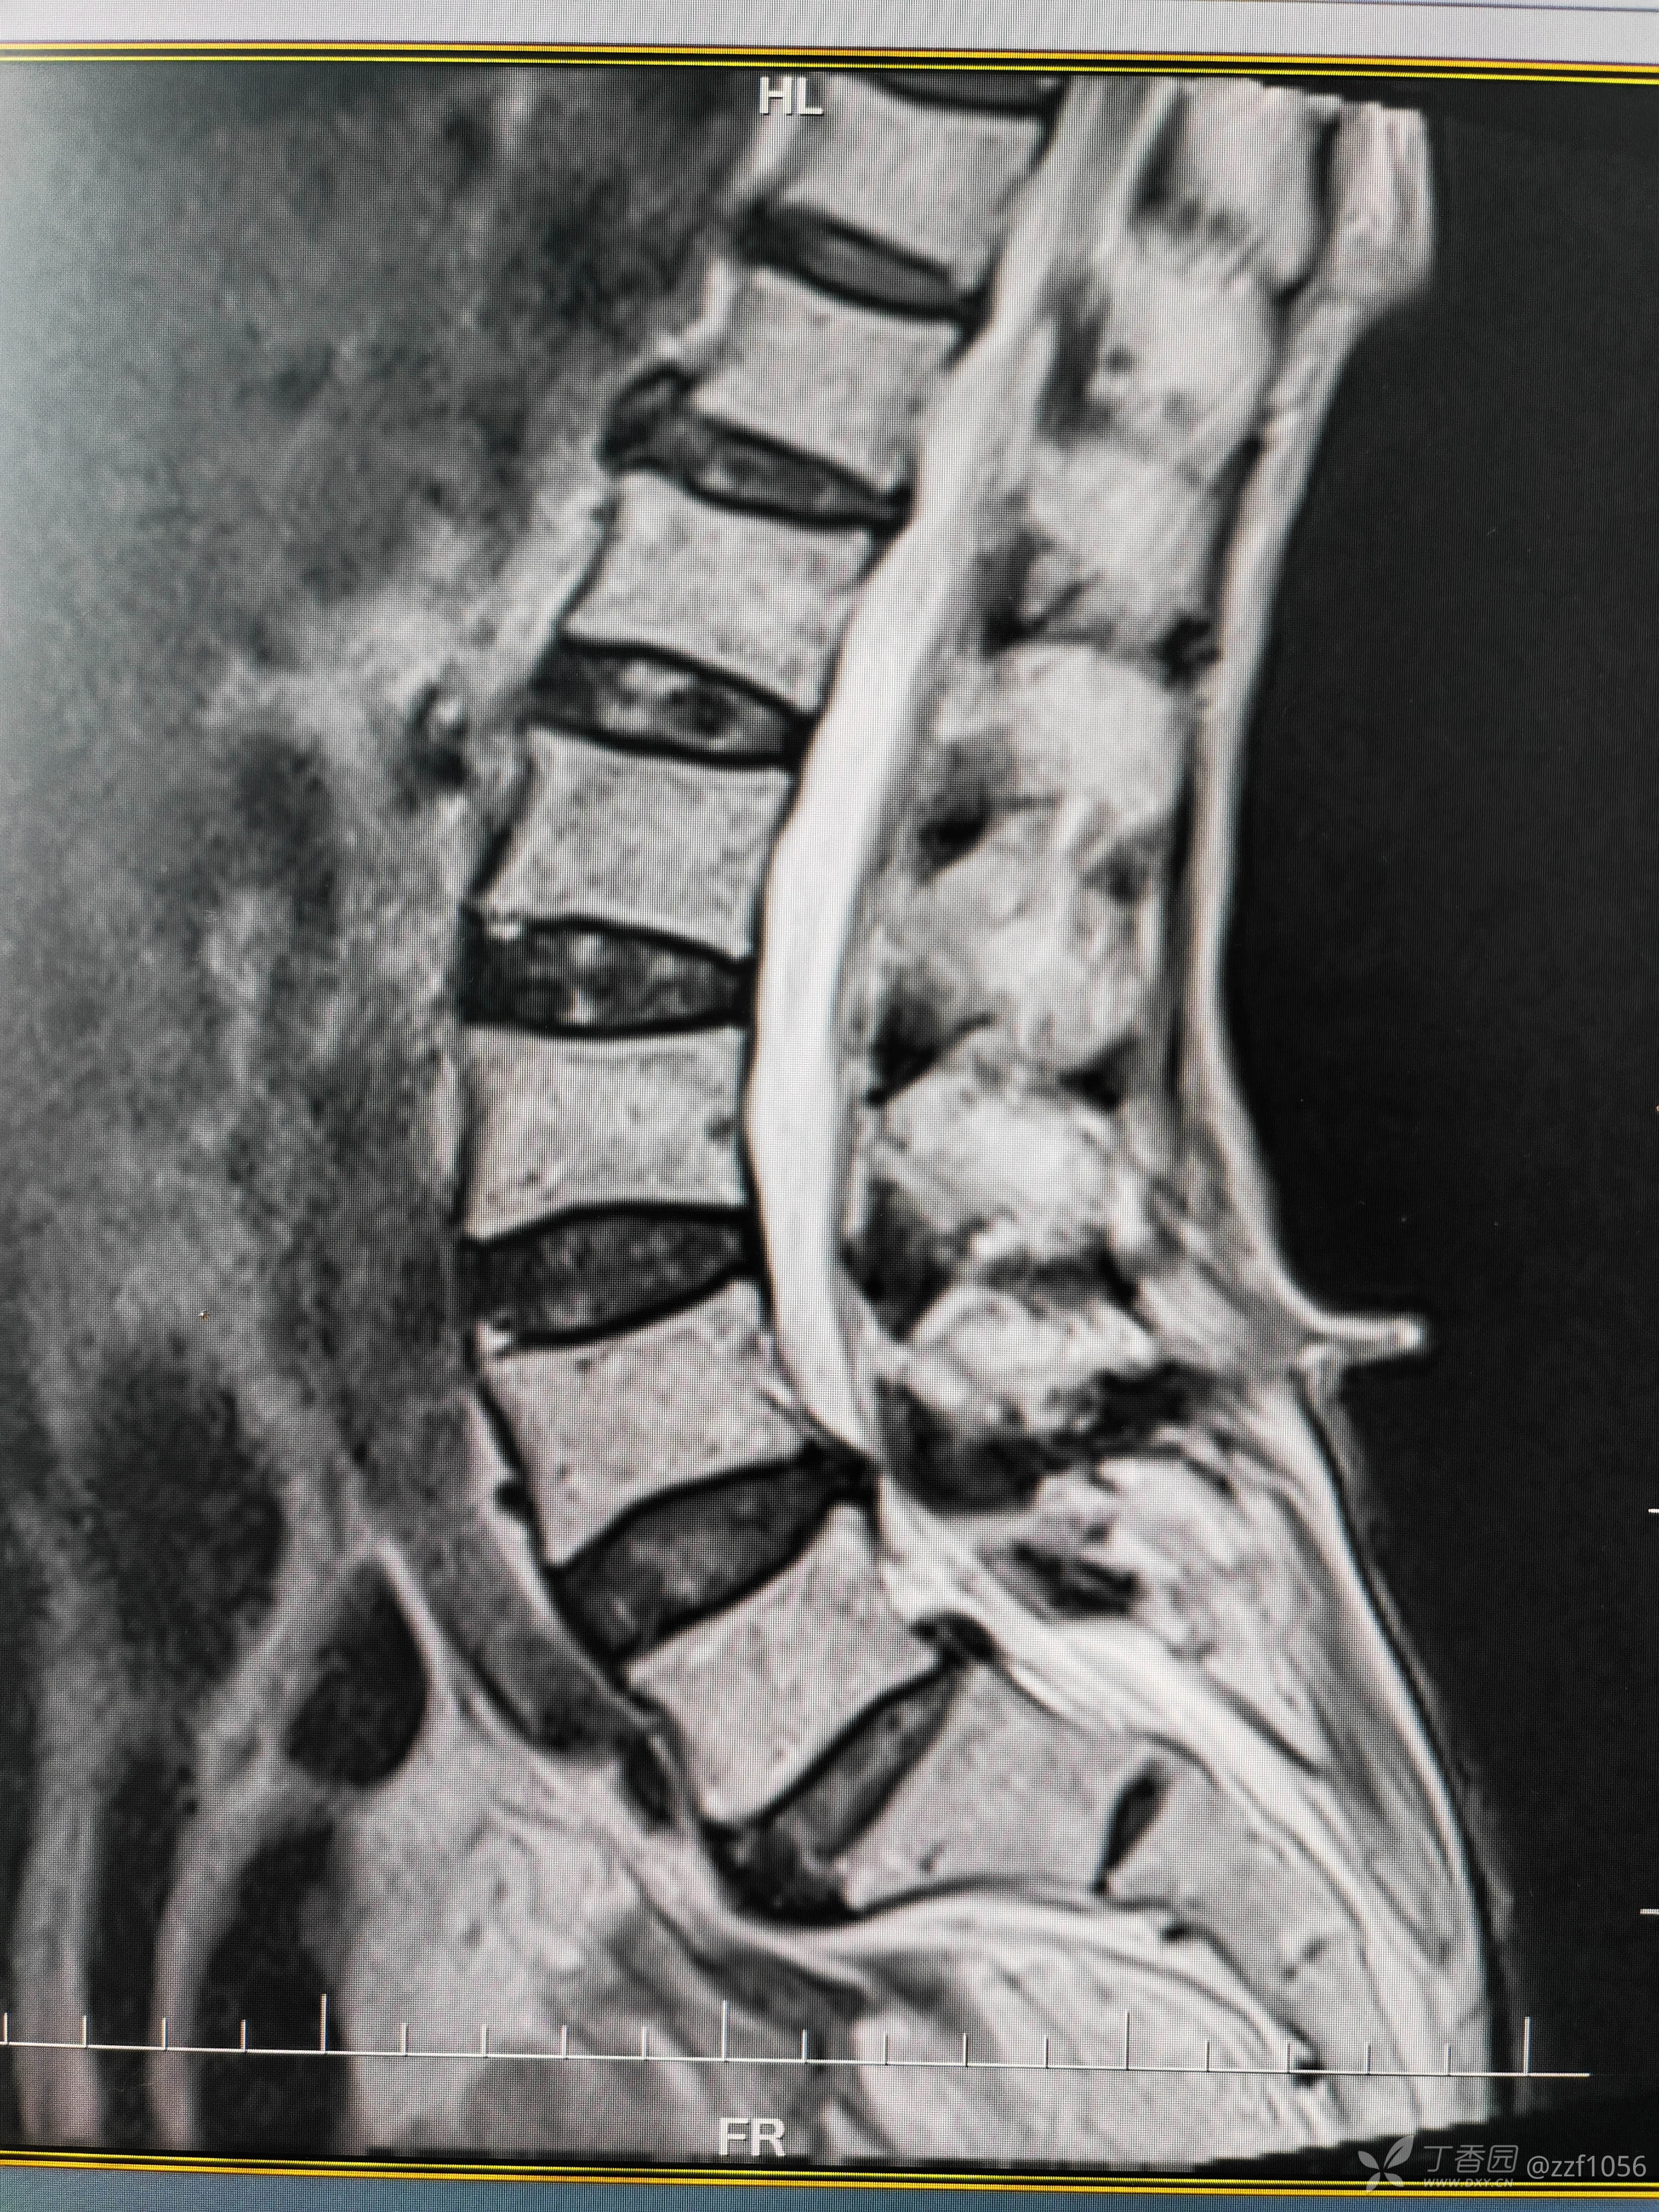

黄韧带肥厚

椎管狭窄

核磁结果L4/5狭窄明显,L5/S1突出存在,仔细查体,高度考虑左下肢L5根症状,其实患者也说不清楚,并且耳背😃